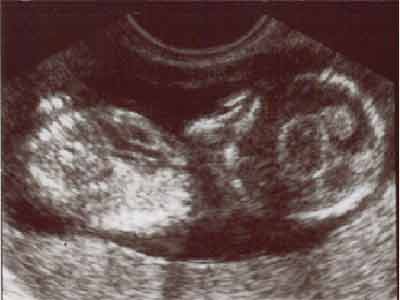

Aorte

Artère pulmonaire